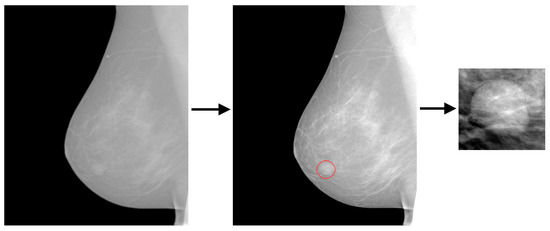

Direct digital mammograms with 97 masses, 65 benign and 32 malignant, were used for training and testing the classifier. This is an in-house FFDM database, the images of which were acquired with a Senographe 2000D or a Senographe Essential FFDM system (GE Healthcare, Chicago, IL, USA). The for-presentation images were used in this study that are either 1914 × 2294 or 2394 × 3062 pixels with 16 bits per pixel (12 bits were allocated). All but nine of the masses came from different mammograms. Nine of the masses were observed on both the mediolateral oblique and the craniocaudal view of the same mammogram and were considered 18 independent findings. Regions of interest (ROIs) were extracted from the full mammograms based on the ground truth files defined by expert mammographers. Figure 10 shows a representative example of ROI extraction. ROIs varied in size because each one was adapted to the mass size so as to encompass the mass and the local background (red circle in Figure 10).

Figure 10.

Extraction of extracted ROI [3].